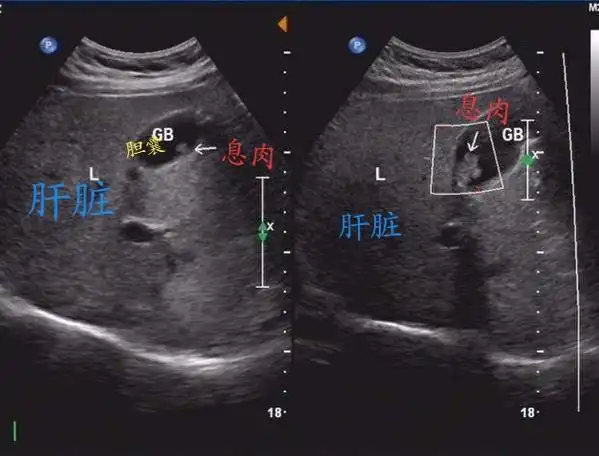

超声显示胆囊壁息肉样病变

胆囊息肉样病变的超声表现